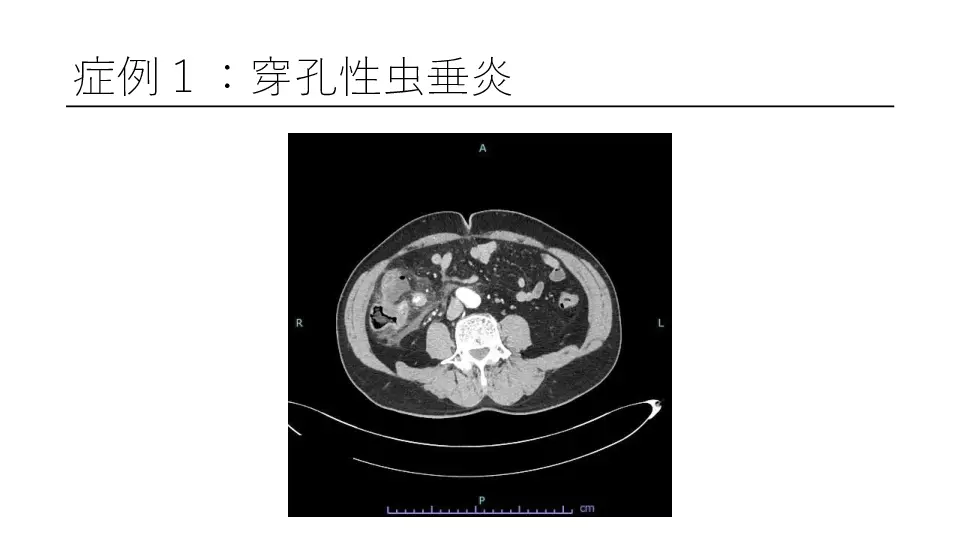

「反跳痛があります」と記載された紹介患者や、研修医からコンサルトにおいて、意外と腹膜炎ではないパターンが散見されます。 若手外科医だからこそ語れる腹膜炎のはなしを聞いてください。 #腹膜炎,#反跳痛の診かた,#コンサルト,